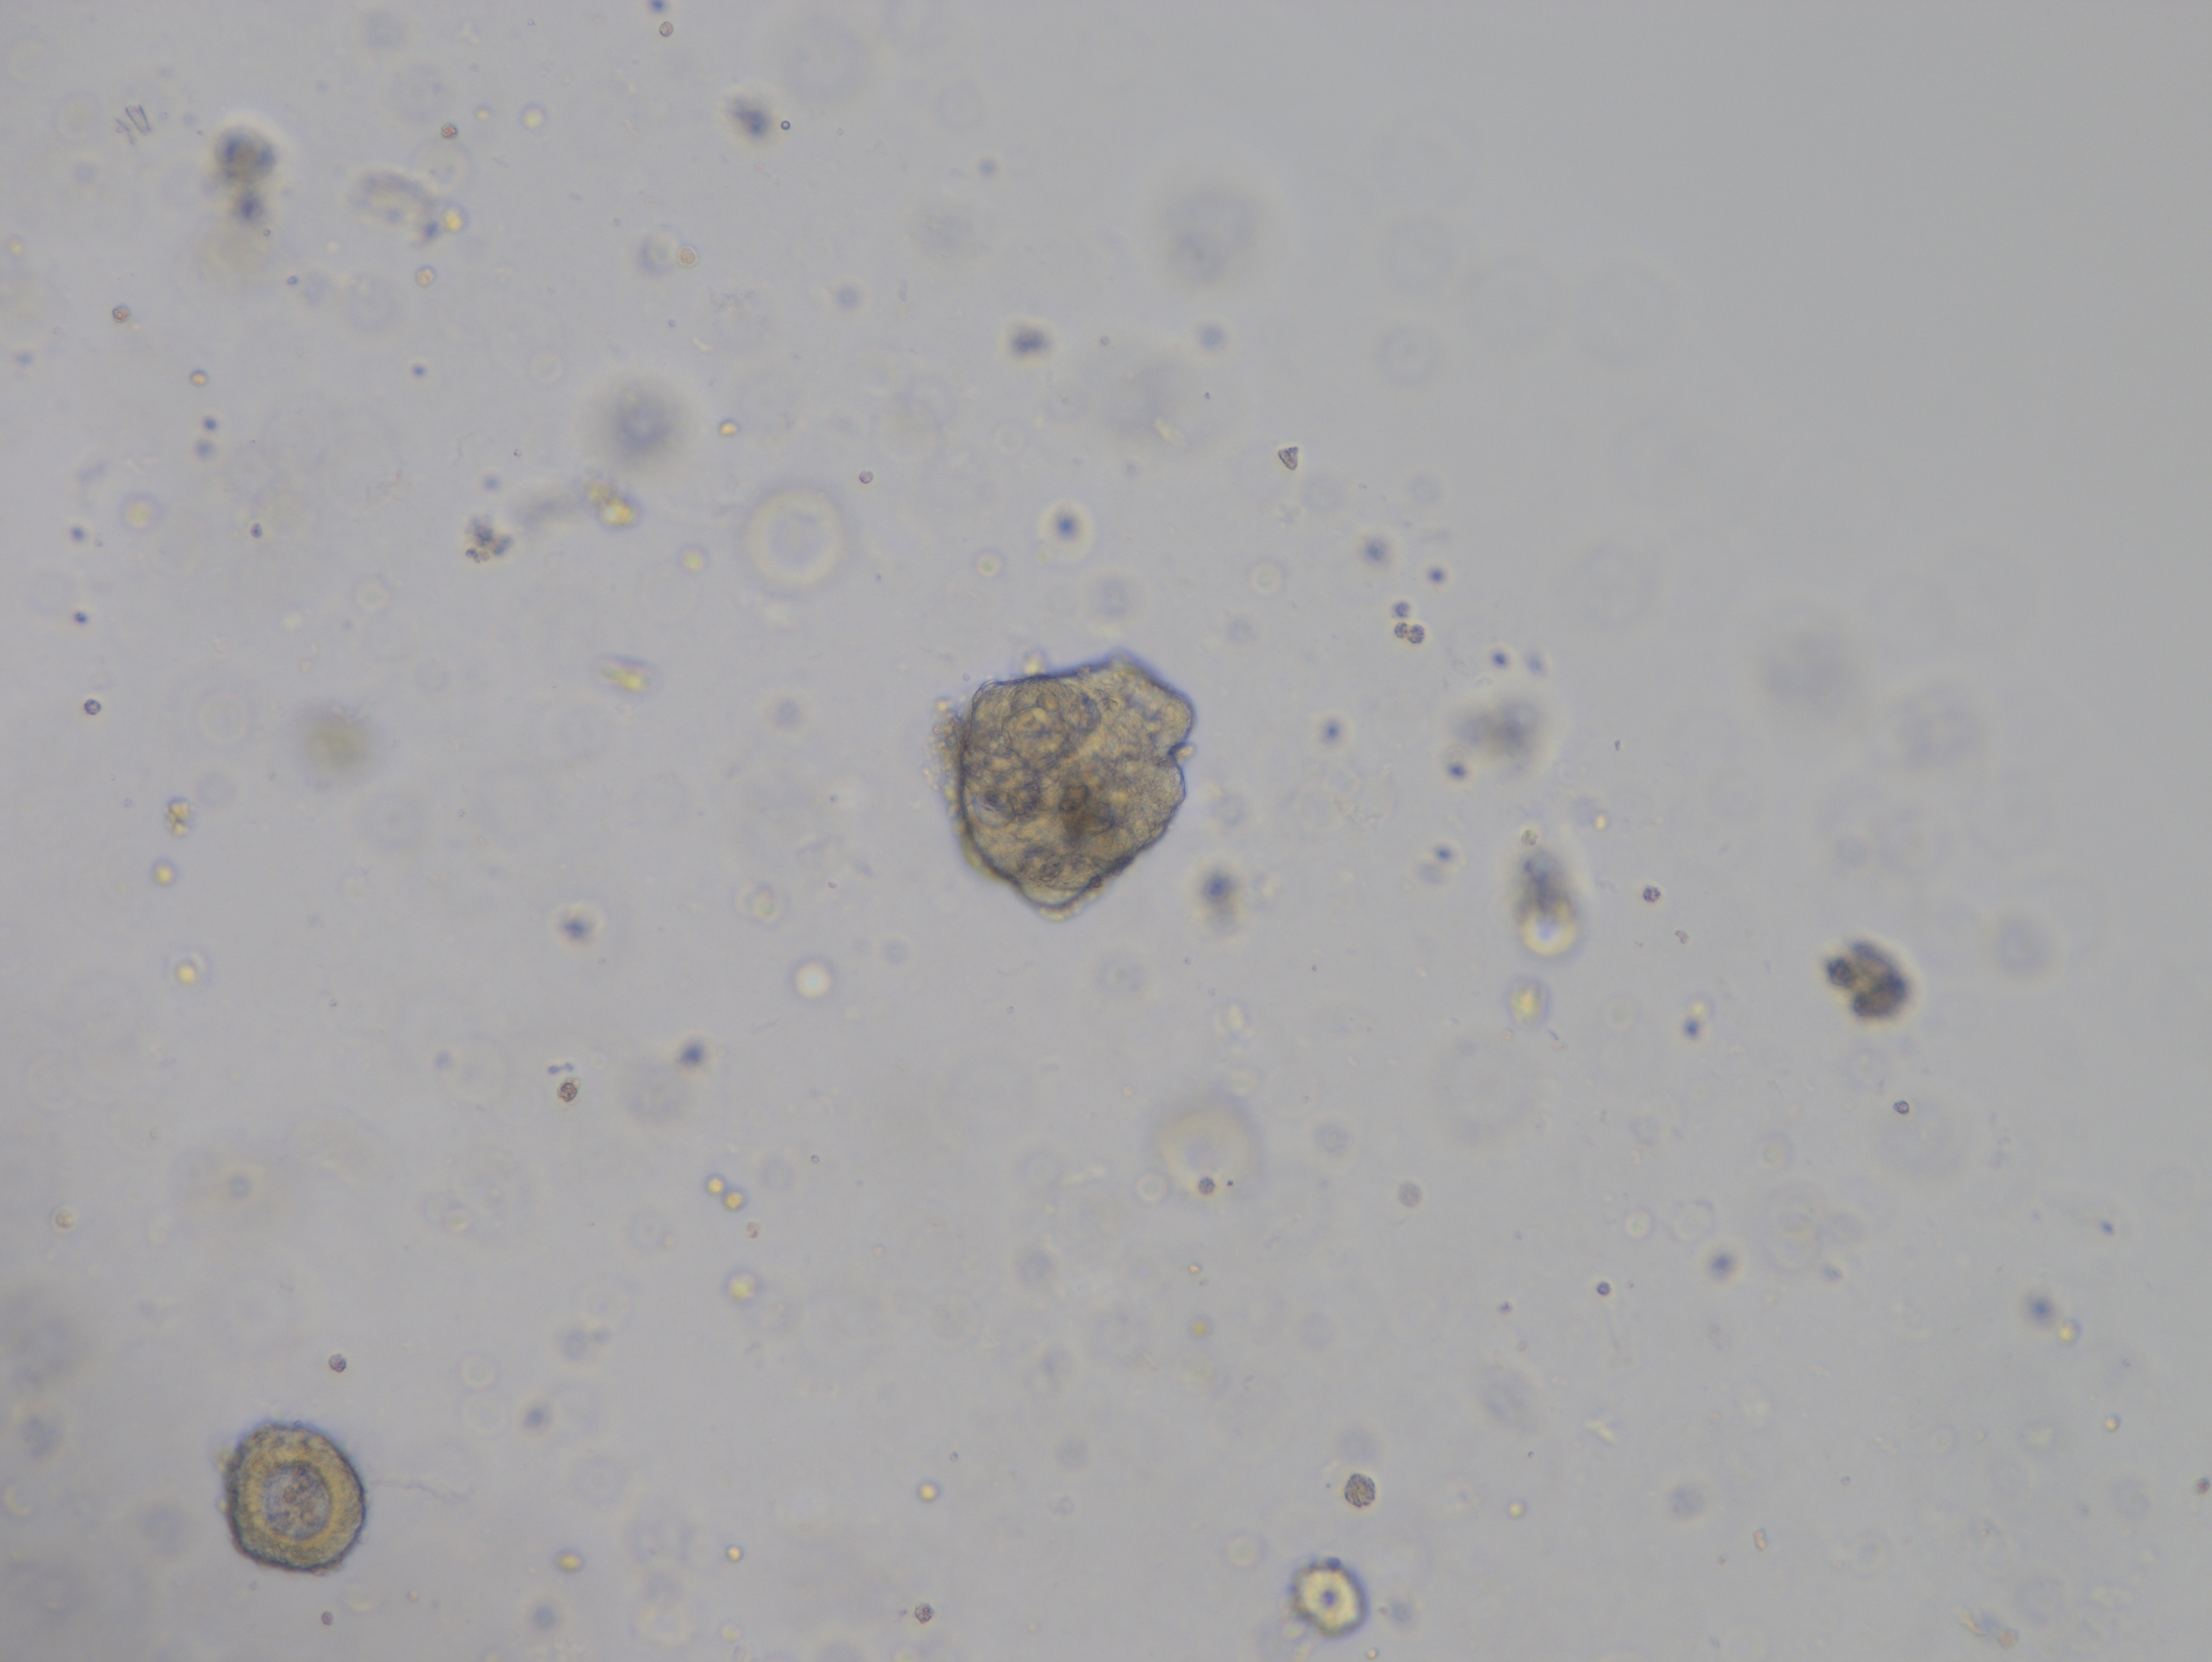

产品介绍 Kinlogix Human Colorectal Cancer Organoid Kit /Medium(人结直肠癌类器官分离培养试剂盒/培养基)是一款用于建立和维持人结直肠癌类器官的完全培养基及试剂。源自患者的癌症类器官可概括原始肿瘤的基因组和病理特征,因此对医学研究和精准医学具有很大的前景。

类器官构建

10. 凝固后加入500ul人结直肠癌类器官培养基到24孔板,置于细胞培养箱中进行培养,每天观察类器官生长情况,每隔1d更换培养液。